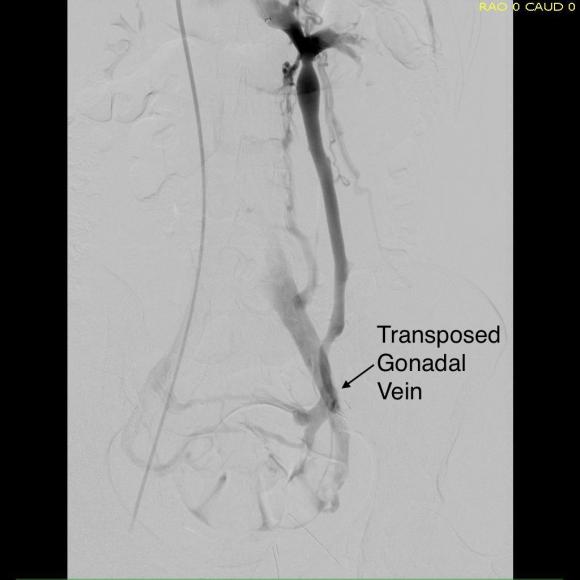

Prior to ligation of the tributaries, a sheath was inserted and through this a LeMaitre valvulotome was brought up to the left renal vein and carefully deployed and pulled back, cutting the valves. This greatly increased the outflow from the vein as evidenced by the height of the blood spout from the vein when the sheath was removed. The varices were ligated at their root -treating them definitively. Transposition was to the external iliac vein, and I could see the feasibility of a laparoscopic or robotic approach to this operation (ref 3).

Completion venography showed excellent flow from the LRV down the gonadal vein into the iliac venous system.